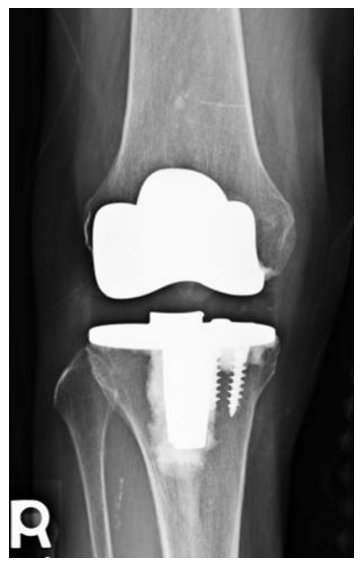

UKA至TKA的翻修被认为是一种相对简单的手术,可能比原发TKA的翻修更有优势。然而,UKA至TKA的翻修通常比原发TKA更具挑战性,大约50%的患者会有明显的骨缺损,33%的病例需要加强固定。UKA失效的模式影响修正的复杂性,但大多数UKA修正可以使用主要组件成功完成(图8),胫骨塌陷的翻修具有最高的复杂性(图9),因为这些病例将更频繁地需要增加和约束。

图8:从以前的UKA翻修到TKA后的术后主要成分X线片。

图9:由于内侧塌陷导致UKA翻修失败后的术后X线片。